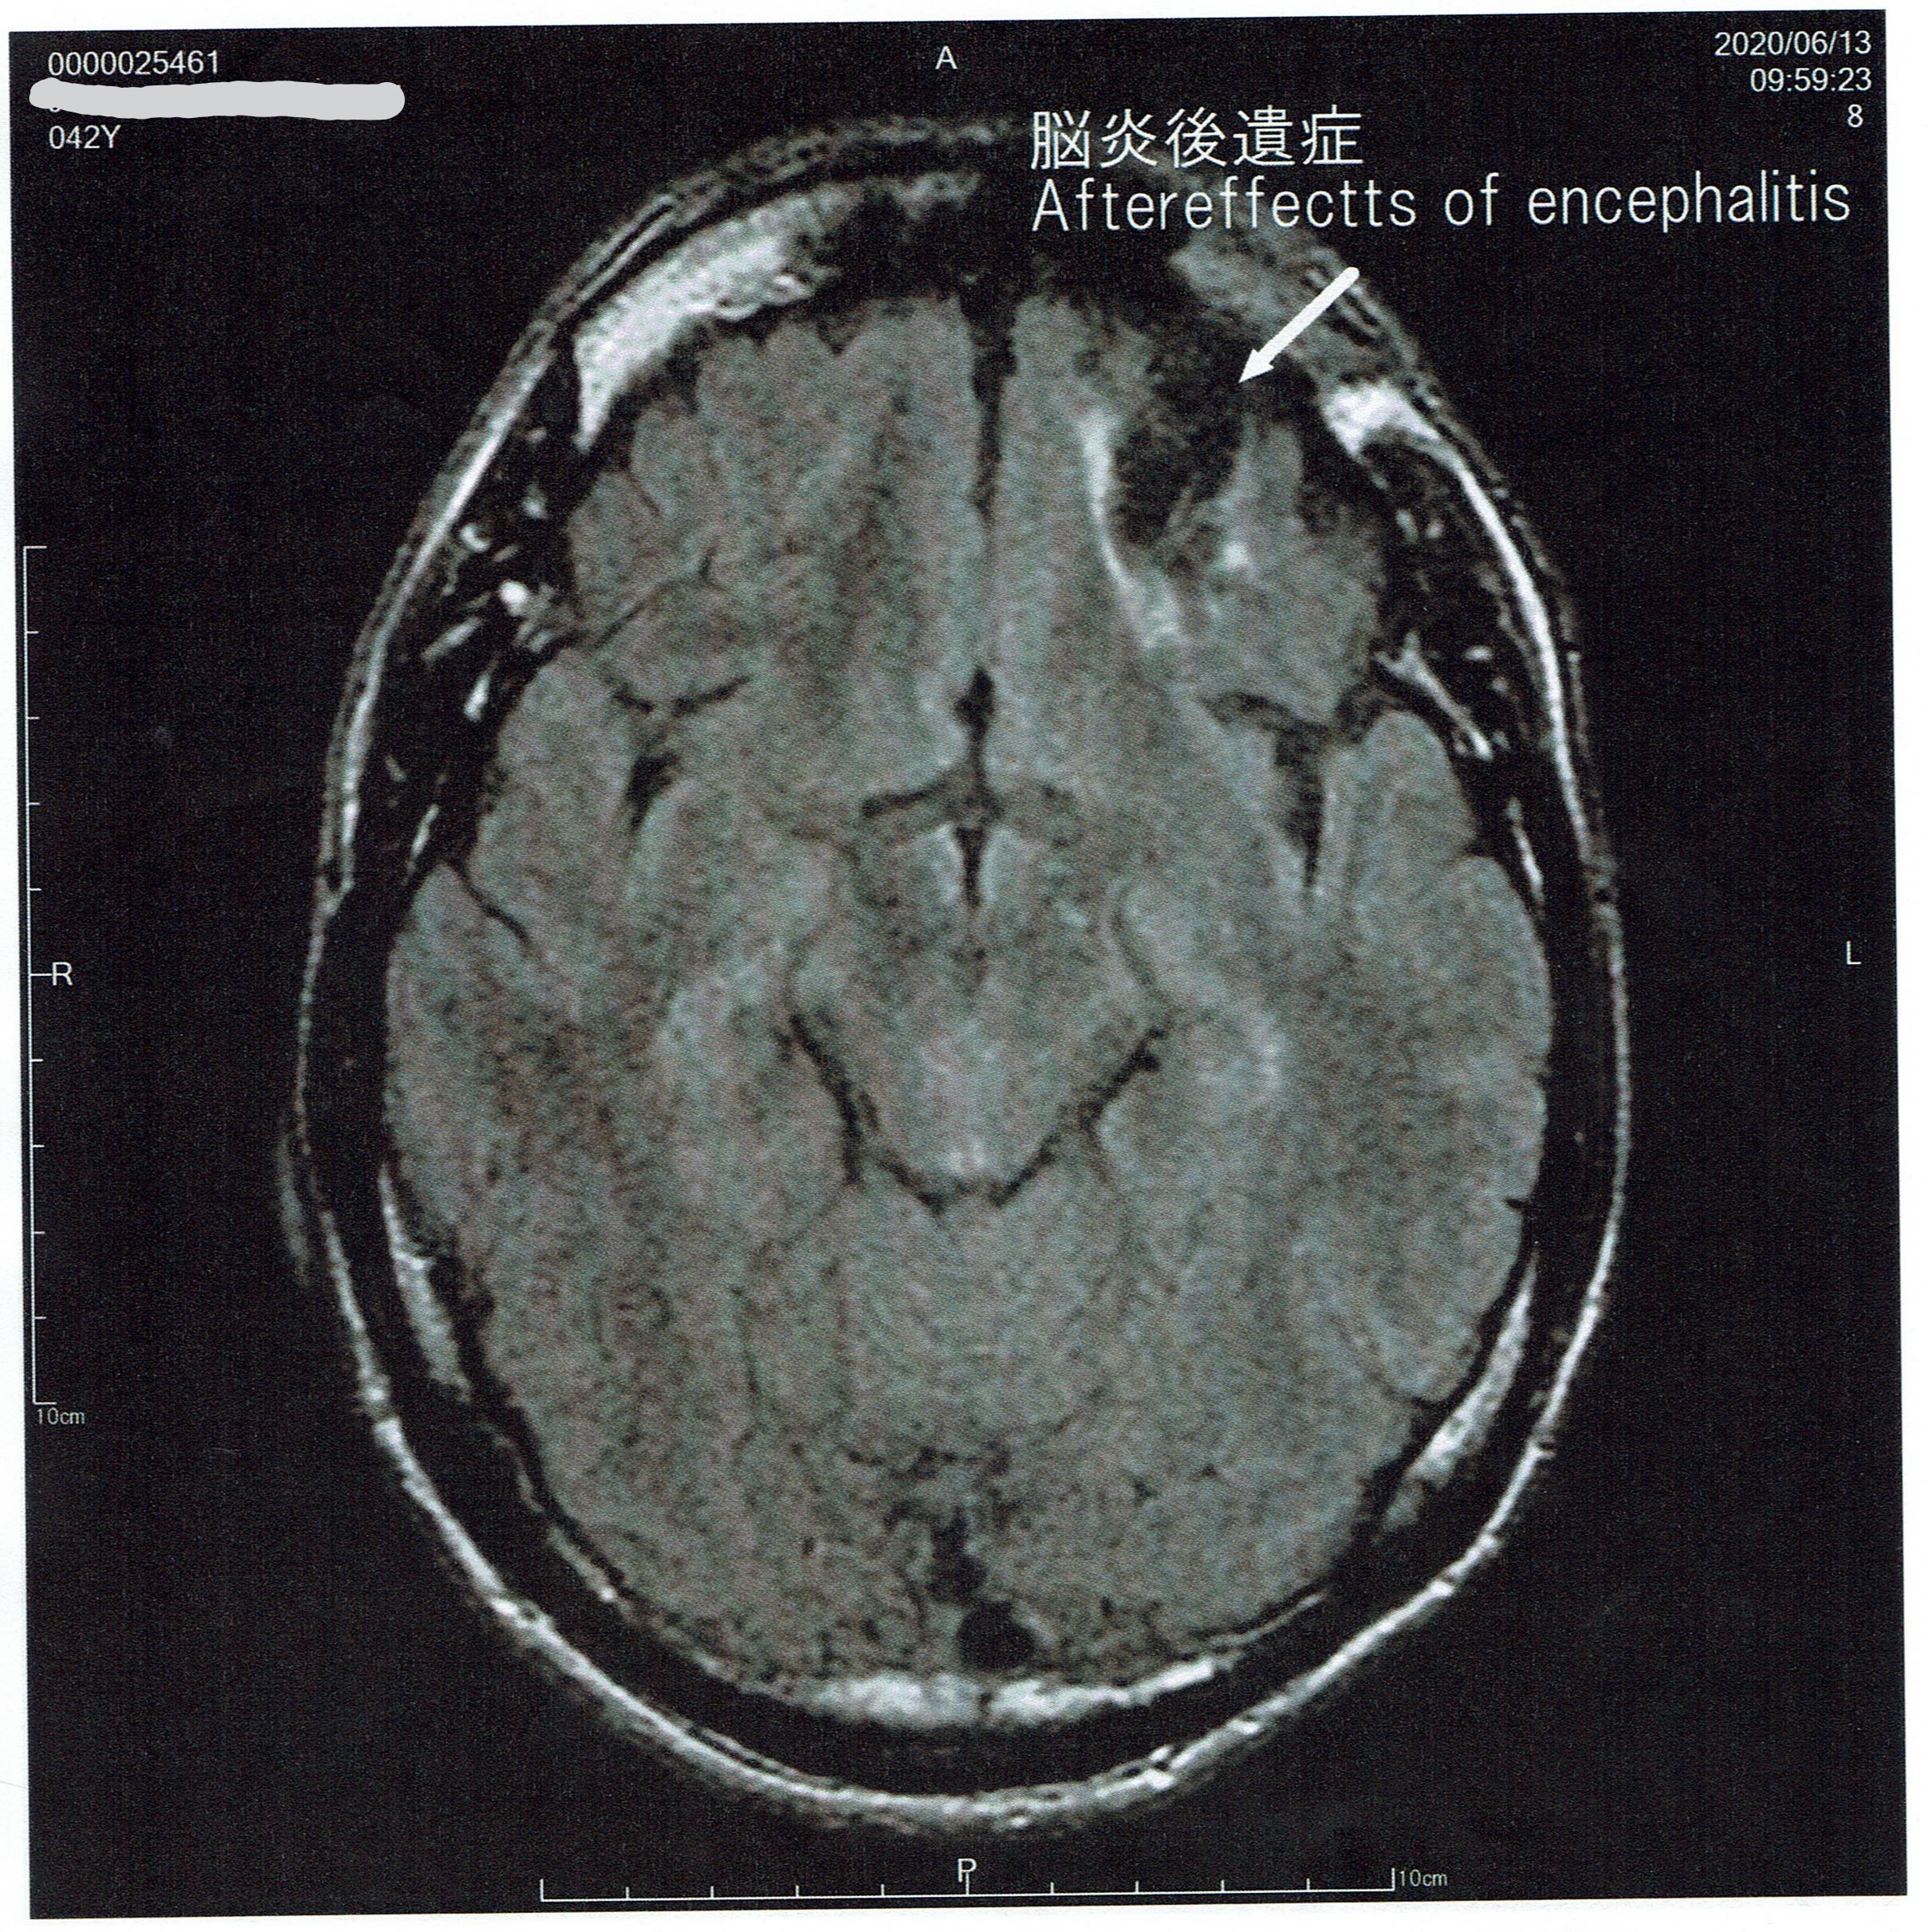

The following MRI were taken more than 25 years after the individual had meningitis.

After effects of encephalitis

Bilateral frontal lobe atrophy

Bilateral parietal lobe atrophy

Extent of atrophy